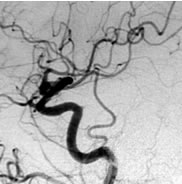

脳動静脈奇形

治療成績は病変の大きさ及び部位によって大きく異なりますが、直径3cm以内のガンマナイフ治療に適した脳動静脈奇形の場合、3年後の完全閉塞率(治癒率)は60−90%前後と報告されています。下図はガンマナイフ治療が奏功し、完全閉塞した典型的な症例です。

ガンマナイフ時の脳血管撮影